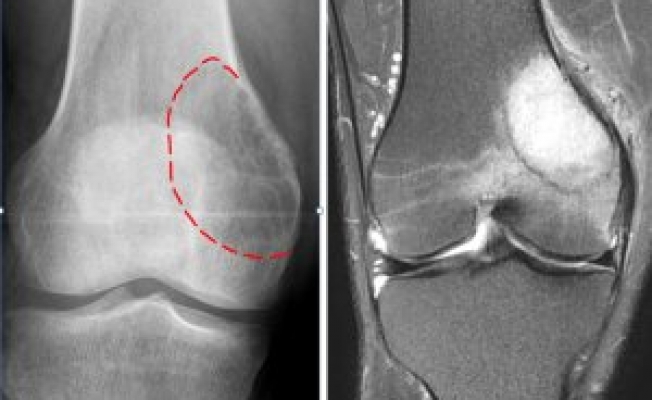

Kemik tümörü olarak adlandırılan Herediter Multipl Ekzositoz (HME) tanısı konulan Birhat, hastanenin ortopedi kliniği doktorları Op. Dr. Recep Dinçer ve ortopedi el cerrahisi uzmanı Op. Dr. Avşin Öztürk tarafından tedavi edildi.

"Vücutta yaygın şekilde tüm ekstremitelerde (kol, bacak) kitle ve çıkıntıların oluşmasıyla fark edilir. Vücuttaki bu yaygın kitleler genel olarak iyi huylu tümörlerden oluşmaktadır. Fakat yüzde 10 kötü huylu tümöre dönüşme ihtimali de vardır. Büyük yumru şeklindeki kitleler ağrıya ve hareket kısıtlılığına yol açarak yüzde 90 oranında günlük yaşam aktivitelerini engeller. Sıklıkla hayatın ilk on yılında görülür."